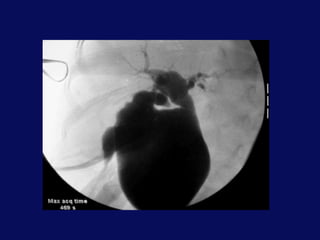

• Intra-operative Cholangiography.

Intra-Oprative

Cholangiography

Surgical Treatment • Intra-operativeCholangiography. • Cyst Excision ( malignant transformation ) . • Roux-en-Y hepatico -jejunostomy . • The limb should be about 50 cm to prevent ascending cholangitis . • Hepatico-duodenosotomy. • Liver biopsy in delayed cases .